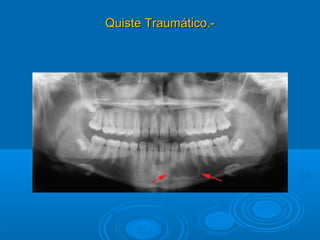

Quiste Traumático.-Quiste Traumático.-

 Patogenia.-Patogenia.- Injuria – se presenta en pacientes jóvenesInjuria – se presenta en pacientes jóvenes

 Edad:Edad: Hombres menores de 20 añosHombres menores de 20 años

 Localización.-Localización.- Mandíbula zona premolar y molar porMandíbula zona premolar y molar por

encima del conducto dentario inferior.encima del conducto dentario inferior.

 TamañoTamaño: de 3 cm. a mas: de 3 cm. a mas

 Forma:Forma: Redondeada u oval MonolocularRedondeada u oval Monolocular

 Imagen radiolúcida.-Imagen radiolúcida.- bordes definidos, pobre corticalbordes definidos, pobre cortical

radiopacaradiopaca

 Produce desplazamientos de dientes o de cortical .Produce desplazamientos de dientes o de cortical .

Dx. DiferencialDx. Diferencial.- Quiste Radicular.- Quiste Radicular

AmeloblastomaAmeloblastoma

Granuloma central de células gigantesGranuloma central de células gigantes